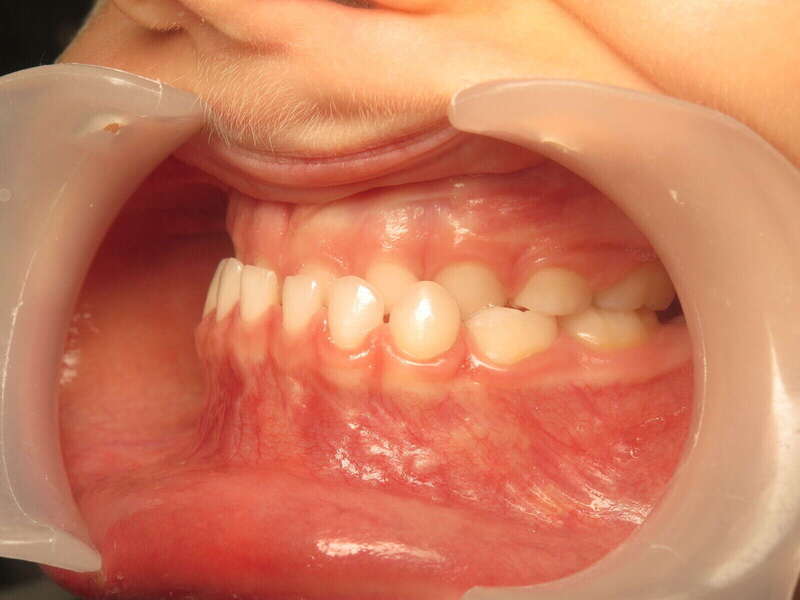

Ce cas d’interception chez un enfant de 8 ans démontre l'efficacité des aligneurs pour corriger des troubles fonctionnels précoces. Le diagnostic présentait des inversions d'articulé provoquant une déviation de la mandibule vers la gauche et un décalage des milieux.

Grâce à une coopération exemplaire et un traitement totalement indolore, l'expansion de l'arcade a permis de recentrer la mâchoire. Cette intervention a littéralement remis la croissance sur les rails, neutralisant le risque d'asymétrie faciale squelettique.

• Correction fonctionnelle : Recentrage immédiat de la mandibule et des milieux inter-incisifs.

• Prévention : Création d'un environnement favorable pour les dents définitives à venir.